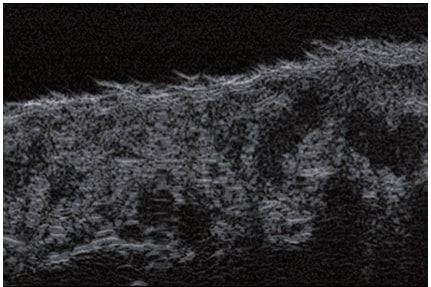

Die Doppler-Sonographie ermöglicht die Darstellung großer Gefäße und Perforatoren, die sich meist in tieferen Bereichen des subkutanen Gewebes befinden. Mit klassischem Ultraschall lassen sich kleinere Gefäße jedoch nicht darstellen. Für die Darstellung kleinerer Gefäße, die oberflächlich unter der Epidermis und im oberen subkutanen Gewebe liegen, wird HFU eingesetzt. Mit Sonden über 20 MHz Frequenz erhält man hochauflösende Ultraschallbilder, auf denen Objekte kleiner als 0,1 mm unterscheidbar sind. Mit zunehmender Auflösung nimmt jedoch die Eindringtiefe ab. Je nach Sonde und Gerät beträgt die maximale Eindringtiefe etwa 20–30 mm. Diese Eindringtiefe bei gleichzeitig hoher Bildauflösung ermöglicht die Beurteilung sehr kleiner Gefäße. HFU erlaubt die genaue Bestimmung des Verlaufs und der Lage kleiner Gefäße in der Haut, was entscheidend für die Wahl der Verschlussmethode und die Planung des Eingriffs ist. Oft sind an der Hautoberfläche nur wenige Gefäße sichtbar – erst durch die Ultraschalluntersuchung lässt sich die tatsächliche Anzahl und der Verlauf feststellen. Für einen erfolgreichen Verschluss muss das gesamte Gefäß behandelt werden, nicht nur der sichtbare Teil, da sonst eine schnelle Rekanalisation erfolgt (7). Häufig ändert das an der Haut sichtbare Gefäß seinen Verlauf, wird gewundener und zieht in tiefere Hautschichten (8). HFU ermöglicht zudem die Darstellung der Perforatoren zwischen kleinen Gefäßen und die Messung grundlegender Parameter wie Durchmesser, Wandstärke, Tiefe und Blutfluss (6). Mit der 40-MHz-Sonde von Ultrasonix kann auch der Blutfluss mittels Farbdoppler visualisiert werden.

Diese Arbeit behandelt die Anwendung von HFU zur Darstellung und zum Verschluss kleiner Venen, d. h. Teleangiektasien und retikulärer Venen. Hochfrequenzsonden >20 MHz ermöglichen die Ultraschalldarstellung der Gefäße in der Dermis und subkutanen Gewebe, was mit klassischen Sonden nicht möglich ist. Ultraschall erfüllt die Erwartungen von Chirurgen und Phlebologen, die bisher keine Möglichkeit hatten, kleine Gefäße zu beurteilen. Traditionelle Durchlichtgeräte waren nur begrenzt einsetzbar, da sie nur oberflächliche Gefäßverläufe zeigten (12). Die Beurteilung von Verlauf, Durchmesser und Tiefe ist entscheidend für die Wahl der Therapie, steigert die Effektivität der Eingriffe und reduziert Komplikationsrisiken. Beim Laser entscheidet das Ultraschallbild über die Wahl des Lasers und die Eingriffsparameter (7). HFU ist auch ein wichtiges Werkzeug zur Überwachung von Eingriffen. Ohne Ultraschallkontrolle wären mikroendovaskuläre Eingriffe oder Mikrosklerotherapie praktisch unmöglich, da sonst ein hohes Risiko für Nekrosen durch Fehlinjektionen besteht.

Hochfrequenz-Ultraschall ist eine nützliche Methode zur Darstellung kleiner Gefäße. Aufgrund der geringen Kosten, Nicht-Invasivität, Mobilität, einfachen Durchführung und Wiederholbarkeit bei Patientensicherheit hat HFU das Potenzial, sich durchzusetzen und in den Alltag einzutreten.